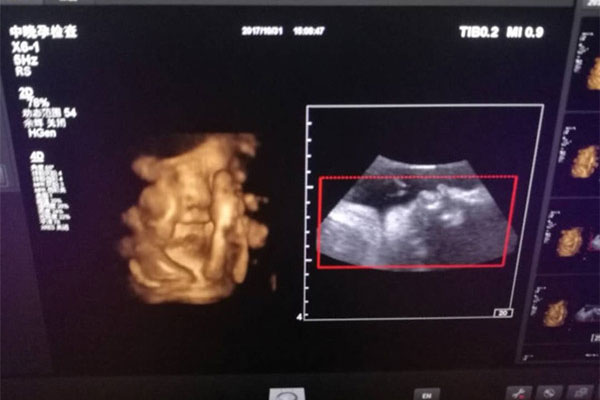

四维彩超,相信很多妈妈都是熟悉的,特别是孕妈妈们都是做过四维彩超的,它与普通B超不同,是非常先进的排畸仪器设备。好友珊珊怀孕刚好26周,前些日子陪着一起去做四维彩超,还好小宝宝比较配合,不到30分钟就做完检查。

在医生照到小宝宝下半身时,我无意中看到屁股下面的两腿之间好像有东西,不知道是男宝的睾丸还是女宝的***。想问问大家,孕26周四维下睾丸的样子 如何看四维彩超识性别呢?

一、孕26周四维下睾丸的样子

其实,四维彩超是可以查看胎儿性别的,只不过国内有明文规定不让鉴定性别,这可是犯法的事情哟。怀孕26周时,胎儿宝宝外生殖器官已经分化出来,通过四维彩超是可以分辨出男孩女孩的。

男胎儿和女胎儿的外生殖器官形态不一样,说简单点就是男孩和女孩的特征点是不同的,男孩的小睾丸和女孩的小***,在B超下看完全是两个不同的东东。一些有经验的妈妈称,男孩的***是吐出来的,而女孩的***是凹进去的,这就是最大的区别不同之处。